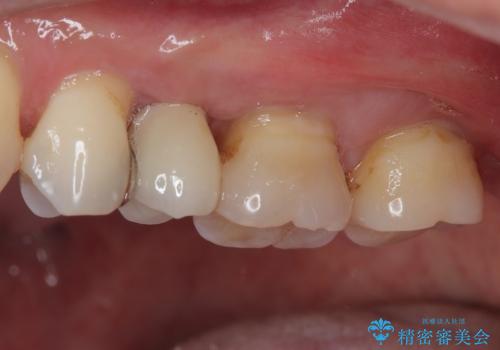

埋入から2ヶ月ほどでインプラントの十分な生着が認められ、処置した歯肉も綺麗に治癒したため、速やかに補綴治療を行いました。

補綴治療後3ヶ月での経過は良好で、引き続き経過観察を行っていきます。